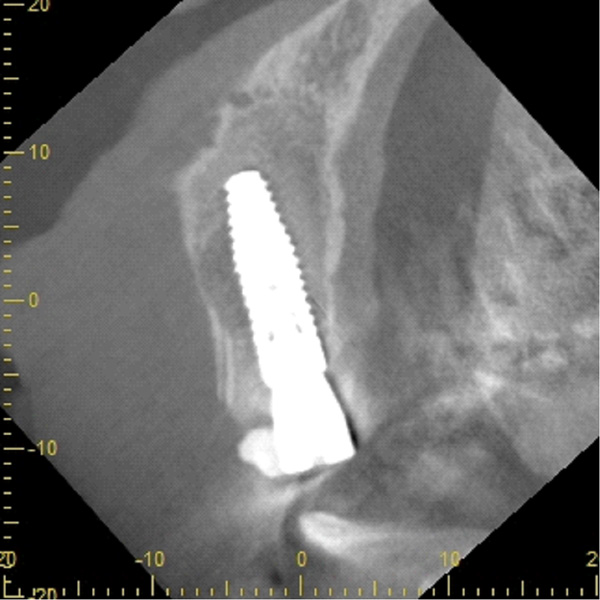

| 年代・性別 | 50代 男性 |

|---|---|

| 主訴 | 前医で前歯を抜かなければならないがインプラントはできないと言われた |

| 治療期間 | 約12ヶ月 |

| 費用 | 600,000円 |

| 治療内容 | インプラント、骨造成、結合組織移植、セラミック修復 |

| 治療に伴うリスク | インプラント周囲炎 セラミックの破折、脱離 |

*キャンセルポリシーをご一読のうえご予約ください